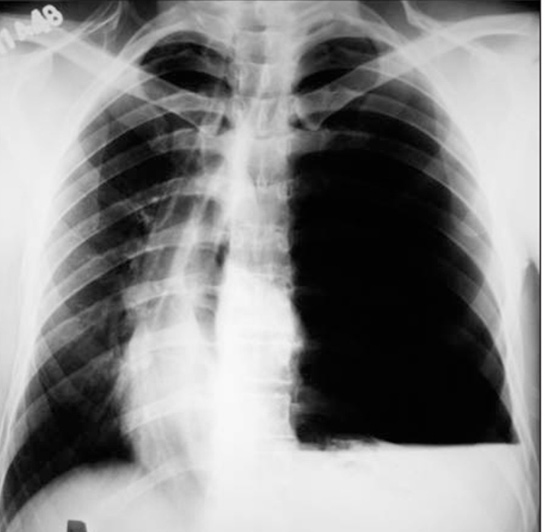

Tansiyon Pnömotoraksın Teşhisi Tansiyon pnömotoraksın teşhisi, klinik muayene ve görüntüleme yöntemleriyle konur. Doktor, hastanın semptomlarını değerlendirir ve aşağıdaki yöntemlerle tanıyı kesinleştirir:

Tansiyon pnömotoraks, akciğerdeki hava boşluğunun artması sonucu göğüs boşluğunda basınç artışına neden olan ciddi bir durumdur. Bu durum, akciğerin çökmesine ve kan dolaşımının bozulmasına yol açabilir.